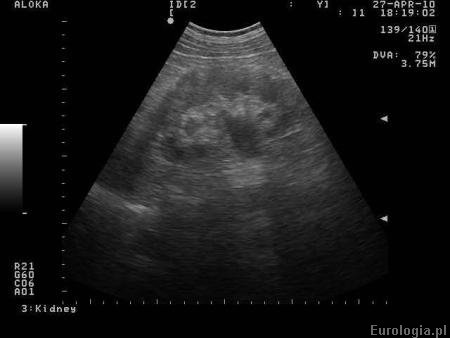

Fot. Prawostronne wodonercze w badaniu USG.

Nie mamy informacji, w którym tygodniu ciąży było wykonane prenatalne USG oraz jaki jest obraz nerek. Najczęstsze przyczyny wodonercza u płodu to:

zwężenie połączenia miedniczkowo - moczowodowego

odpływ pęcherzowo - moczowodowy

moczowód olbrzymi

zastawki cewki tylnej

nerka podwójna z towarzszącym refluksem lub obstrukcyjnym ureterocele

Dalsze postępowanie uzależnione jest od stopnia poszerzenia układu kielichowo - miedniczkowego oraz stanu ogólnego dziecka. Decyzja o postępowaniu podejmowana jest po kilku kontrolnych badaniach USG.